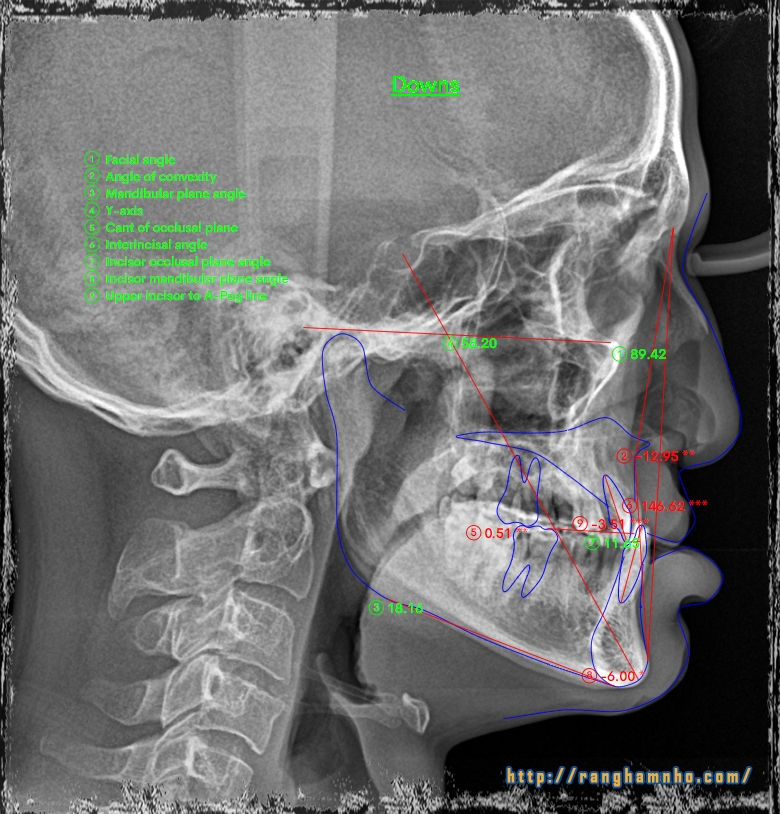

BN khớp cắn hạng 3, hàm trên nằm trọn trong hàm dưới. Hàm trên cực hẹp. Chỉ định nong hàm với ốc nong nhanh và dây Damon. Dựng trục răng 7 hàm dưới, torque lại trục răng hàm trên, giải “hẹp” hàm trên, kéo răng lệch phía khẩu cái ra ngoài. Giải khớp cắn ngược răng cửa, cắn kéo R7, tất cả dùng dây cung thẳng liên tục.